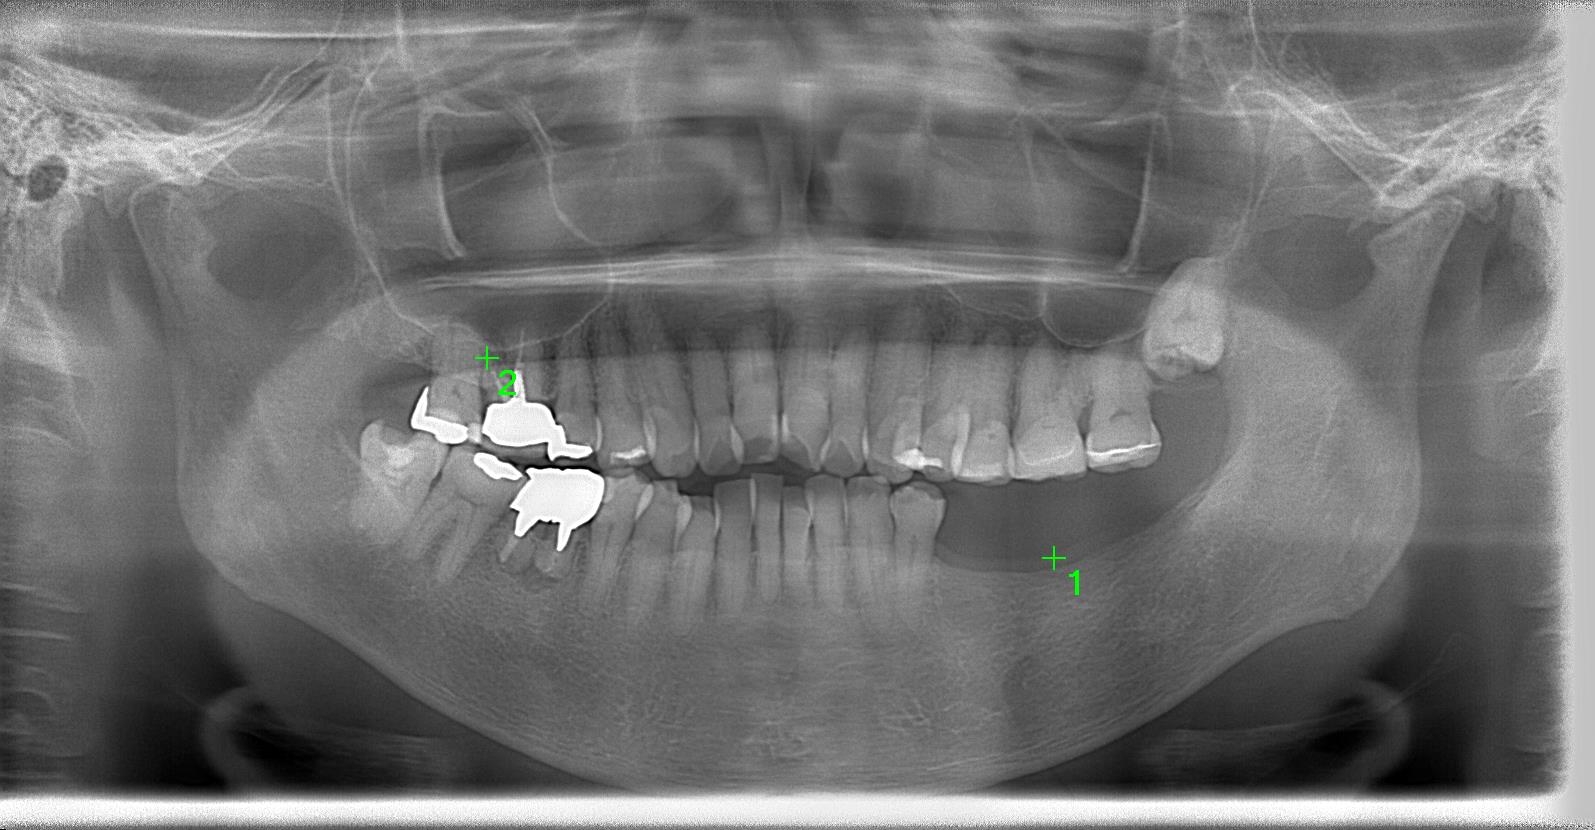

術前パノラマレントゲン写真